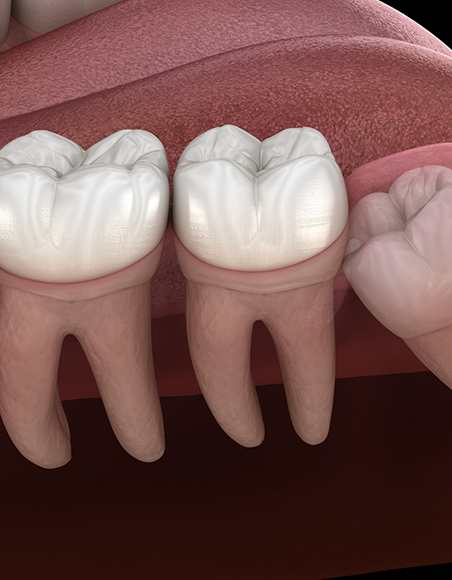

Wisdom teeth, also called the third molars, are the last set of teeth to erupt at the back of the mouth, and they often make their appearance during the teenage years or early adulthood. While some lucky individuals have room in their mouth for wisdom teeth (or don’t have them at all), most of us end up needing to have the teeth removed before they begin causing oral health issues. Luckily, the wisdom tooth extraction process is incredibly straightforward and something our team is happy to guide you or a family member through. To get started, contact our Encinitas dental office!

The wisdom tooth extraction process is relatively straightforward, even when multiple wisdom teeth need to be extracted. After the mouth is numbed (sedation dentistry is also often used), if the teeth have emerged above the gumline, they can be carefully removed with special forceps. If they’re still beneath the gums, small openings can be made to access them, and from there, they’re often removed in small pieces to make things easier. Patients will need to endure a brief healing period following the procedure.